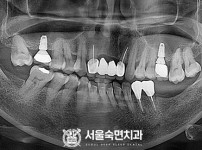

임플란트-전후사진2

임플란트-전후사진3